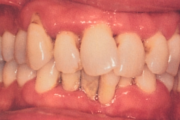

- igemepiir on taandunud (3)

- vahed hammaste vahel (5)

- puuduvad hambad/hammas (4)